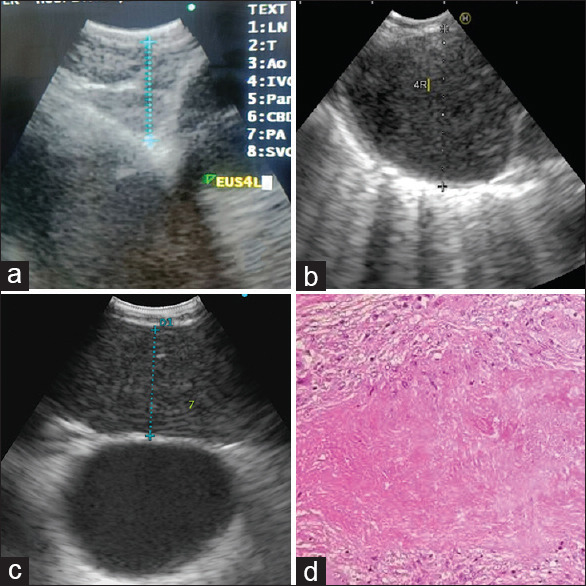

Background: Mediastinal Tuberculosis (TB), although a common presentation of TB in children, has a very low rate of microbiological confirmation. This is because of the difficulty in acquiring appropriate tissue samples for microbiological confirmation. Endobronchial ultrasound (EBUS) and esophageal ultrasound with a bronchoscope (EUS-B) offer a safe, effective, and minimally invasive modality of sampling in these children. We present our institutional experience on EBUS/EUSB and the various ancillary investigations for mediastinal TB.

Methods: This is a single-center retrospective study among children who underwent EBUS/EUS-B for a mediastinal nodal lesion. The primary objective of the study was to analyze the diagnostic accuracy of histopathology and various microbiological investigations, through EBUS/EUS-B guided TBNA, in the diagnosis of mediastinal TB. The secondary objective was to ascertain the safety of EBUS/EUS-B.

Results: A total of 50 children underwent EBUS/EUS-B at our center, of those 26 (17 girls, mean age 11.7 years) were diagnosed with mediastinal TB. Fever was the most common presenting symptom (85%) and only seven children (26%) had a concomitant pulmonary involvement. The diagnostic performance of various investigations was as follows: Acid-fast bacilli (AFB) smear (sensitivity - 86.6%, specificity - 82.9%, NPV-93.5%, PPV - 68.4%), Xpert Ultra (sensitivity -100%, specificity - 68.5%, NPV - 100%, PPV - 57.7%), and cytology (sensitivity - 100%, specificity - 82.9%, NPV - 100%, PPV - 71.4%). A microbiological confirmation was attained in 81% of the children. There were no major complications in any of the procedures.

Conclusion: EBUS/EUSB is an effective and safe investigation for the diagnosis of mediastinal TB in children.